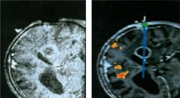

Nachteile der Realzeit-Schichtbilder sind die lange Scannzeit, ca. 2-5 Sekunden, und die vor allem bei

Kernspintomographen mit niedriger Feldstärke (0,2 oder 0,5 Tesla) schlechte Bildqualität. In der

Abbildung ist links ein Realzeit-Schichtbild (0,5 Tesla) und recht ein aus einem präoperativen

3D-Datensatz ermitteltes Bild dargestellt (3D-Sequenz, 0,5 Tesla).

Wichtig ist, dass es sich für den Arzt bezüglich dieser beiden Bildmodalitäten nicht

um eine Entweder-Oder-, sondern vielmehr um eine Sowohl-Als-Auch-Betrachtung handelt. So wird durch das

rechte Bild ein Bezug zur Planung hergestellt, und durch das linke Realzeit-Schichtbild kann die

"Güte" dieser eigentlich "veralteten" Bilddaten beurteilt werden.